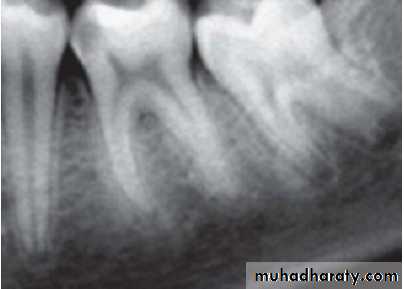

2. Radiographic findings:

– May show depth and extent of caries.– Periapical area shows normal appearance but a slight widening may be evident in advanced stages of pulpitis.